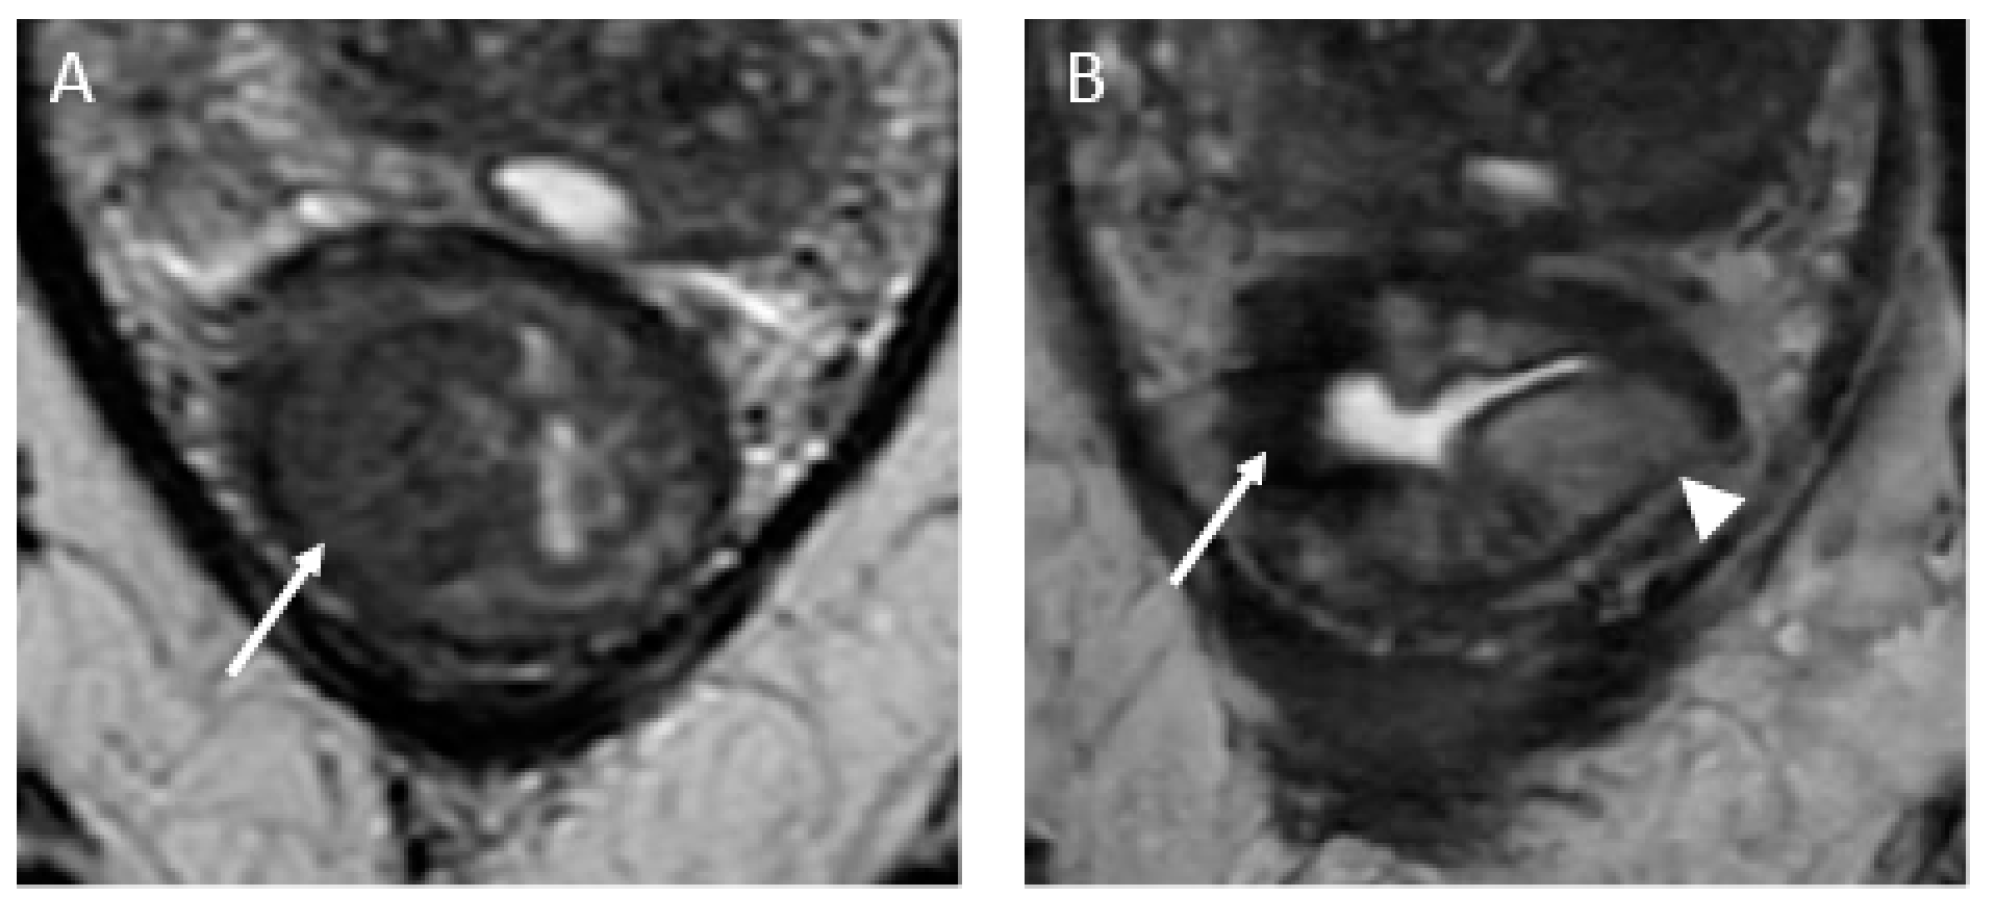

Near-complete response in a 65-year-old man with middle rectal adenocarcinoma. (A) Baseline axial T2-weighted MR image shows an intermediate-signal-intensity, near-circumferential low rectal tumor (dotted line). (B) Axial T2-weighted MR image after the completion of neoadjuvant chemoradiotherapy shows a slight response with a small amount of fibrosis and residual tumor signal intensity (arrow). Axial diffusion-weighted image (C) shows high signal intensity (arrowhead), and the axial apparent diffusion coefficient map (D) shows a corresponding low signal intensity (arrowhead), in keeping with restricted diffusion at the nonfibrotic portion of the tumor.